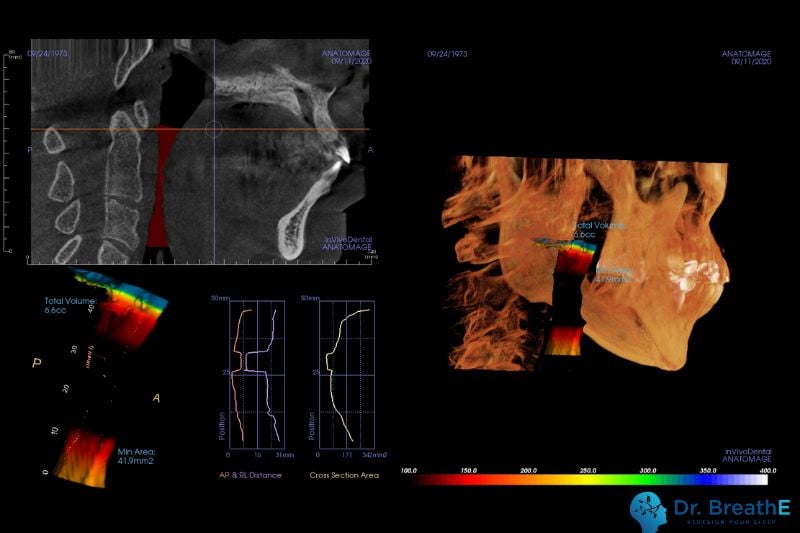

- 呼吸道電腦斷層:現在可以透過電腦斷層評估你的呼吸道空間,確認呼吸道結構是否狹窄、阻塞,幫助醫師判斷是否需要進一步處理呼吸道問題。

後來,楊先生來到丰采美學牙醫的睡眠特別診所進行進一步評估。診所的醫師發現,楊先生的下巴明顯後縮,結構性問題導致他的呼吸道空間受限。再加上他長期以來習慣用口呼吸,使得舌頭和口腔肌肉的支撐力不足,進一步加劇了睡眠期間的呼吸道塌陷,導致呼吸阻礙。醫師解釋,楊先生的情況是典型的『結構性』睡眠障礙,需要透過專業的結構性治療和功能性訓練來改善。